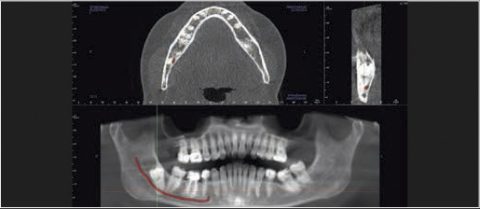

Tomografia cyfrowa z jeszcze bardziej innowacyjną technologią Dose Reduction Technology™ (DRT) urządzenia GXDP-800™ CBCT umożliwia wykonywanie zoptymalizowanych obrazów rentgenowskich 3D / tomograficznych przy zastosowaniu małej dawki promieniowania RTG. Zmniejszenie dawki promieniowania to istotna korzyść w określonych przypadkach klinicznych takich jak obrazowanie pooperacyjne, wstępne planowanie wszczepienia implantu czy obrazowanie RTG u dzieci.

Cztery różne pola obrazowania zapewniają niezawodną diagnostykę 3D w całym obszarze jamy ustnej. Zapewniają one precyzyjne dopasowanie, odpowiednie do wskazań a także uniwersalne możliwości zastosowania w codziennej praktyce – od endodoncji, poprzez implantologię do chirurgii jamy ustnej.